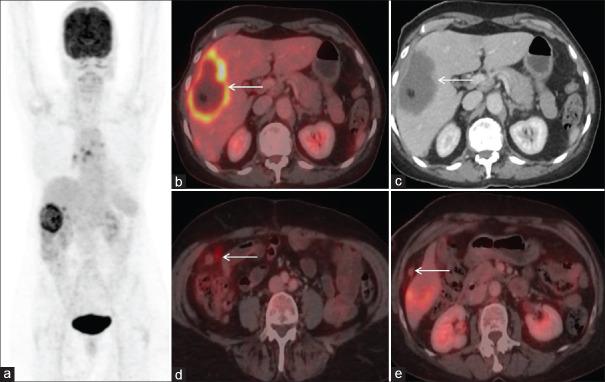

Role of FDG PET/CT in evaluation of biliary tract diseases remains relatively unexplored. PET/CT with FDG helps in evaluation of both infective / inflammatory as well as neoplastic diseases as increased glucose utilization is observed in both the conditions. In this article, we describe the spectrum of FDG PET/CT findings in various diseases affecting the biliary tract. Role of FDG PET/CT in neoplastic diseases involving the biliary duct has been described at the time of staging and response evaluation; in characterization of the intrahepatic mass (abscess v/s cholangiocarcinoma). In addition, we have discussed about the false positive FDG uptake along the biliary duct stent, which interfere with scan interpretation. Few of the benign conditions described are Langerhans cell histiocytosis and IgG4 related disease involving the biliary duct and adenomyomatosis and Xanthogranulomatous cholecystitis involving the gall bladder.

氟代脱氧葡萄糖正电子发射断层显像/计算机断层扫描(FDG PET/CT)在胆道疾病评估中的作用仍相对未被充分探索。含氟代脱氧葡萄糖的PET/CT有助于评估感染性/炎症性疾病以及肿瘤性疾病,因为在这两种情况下均观察到葡萄糖利用率增加。在本文中,我们描述了FDG PET/CT在影响胆道的各种疾病中的表现谱。FDG PET/CT在胆管肿瘤性疾病分期和疗效评估以及肝内肿块(脓肿与胆管癌)鉴别诊断中的作用已被阐述。此外,我们还讨论了沿胆管支架出现的FDG摄取假阳性情况,这会干扰扫描结果的解读。所描述的一些良性疾病包括累及胆管的朗格汉斯细胞组织细胞增多症和IgG4相关疾病,以及累及胆囊的腺肌增生症和黄色肉芽肿性胆囊炎。